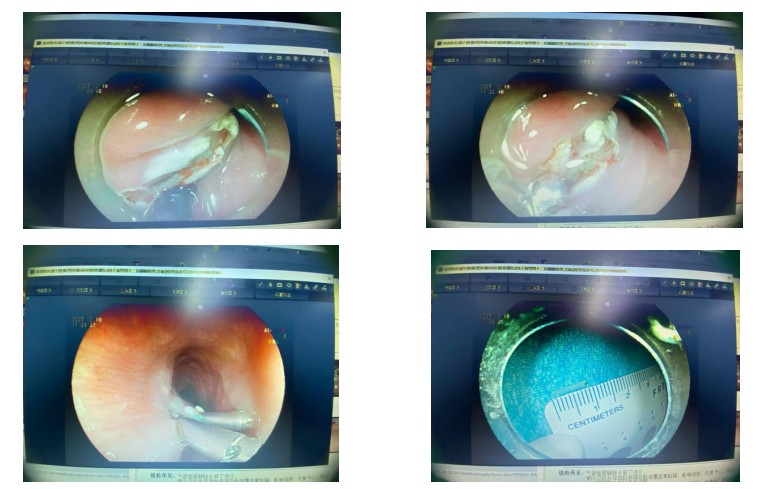

据了解,该患者进食时不慎误吞鱼刺,初期未予重视,还尝试用大量饭菜强行下咽,随后逐渐出现咽部剧痛、吞咽困难症状,甚至伴随胸部隐痛不适,遂在家属陪同下紧急前往南溪山医院消化内科就诊。经胃镜及食管 CT 检查确诊,一根鱼刺已完全刺入食管壁,诱发局部黏膜充血水肿,且形成局限性脓肿,鱼刺深埋食管壁内无法通过普通内镜直接观察,若延误治疗,极有可能引发食管穿孔、纵隔感染等致命并发症,危及生命安全。

考虑到传统外科手术创伤大、恢复周期长,会给患者带来较大身心负担,消化内科医疗团队第一时间组织病例研讨,结合患者病情精准评估,最终敲定内镜下微创治疗方案。手术中,医护团队凭借精湛内镜操作技术,先通过超声胃镜精准锁定鱼刺埋藏位置,再运用 ESD 技术小心切开局部黏膜,借助圈套器、异物钳精准操作,将刺入食管壁的鱼刺完整取出,随后对脓肿部位进行彻底引流。整个手术过程顺利,耗时短、创伤小,患者术中无明显不适感。